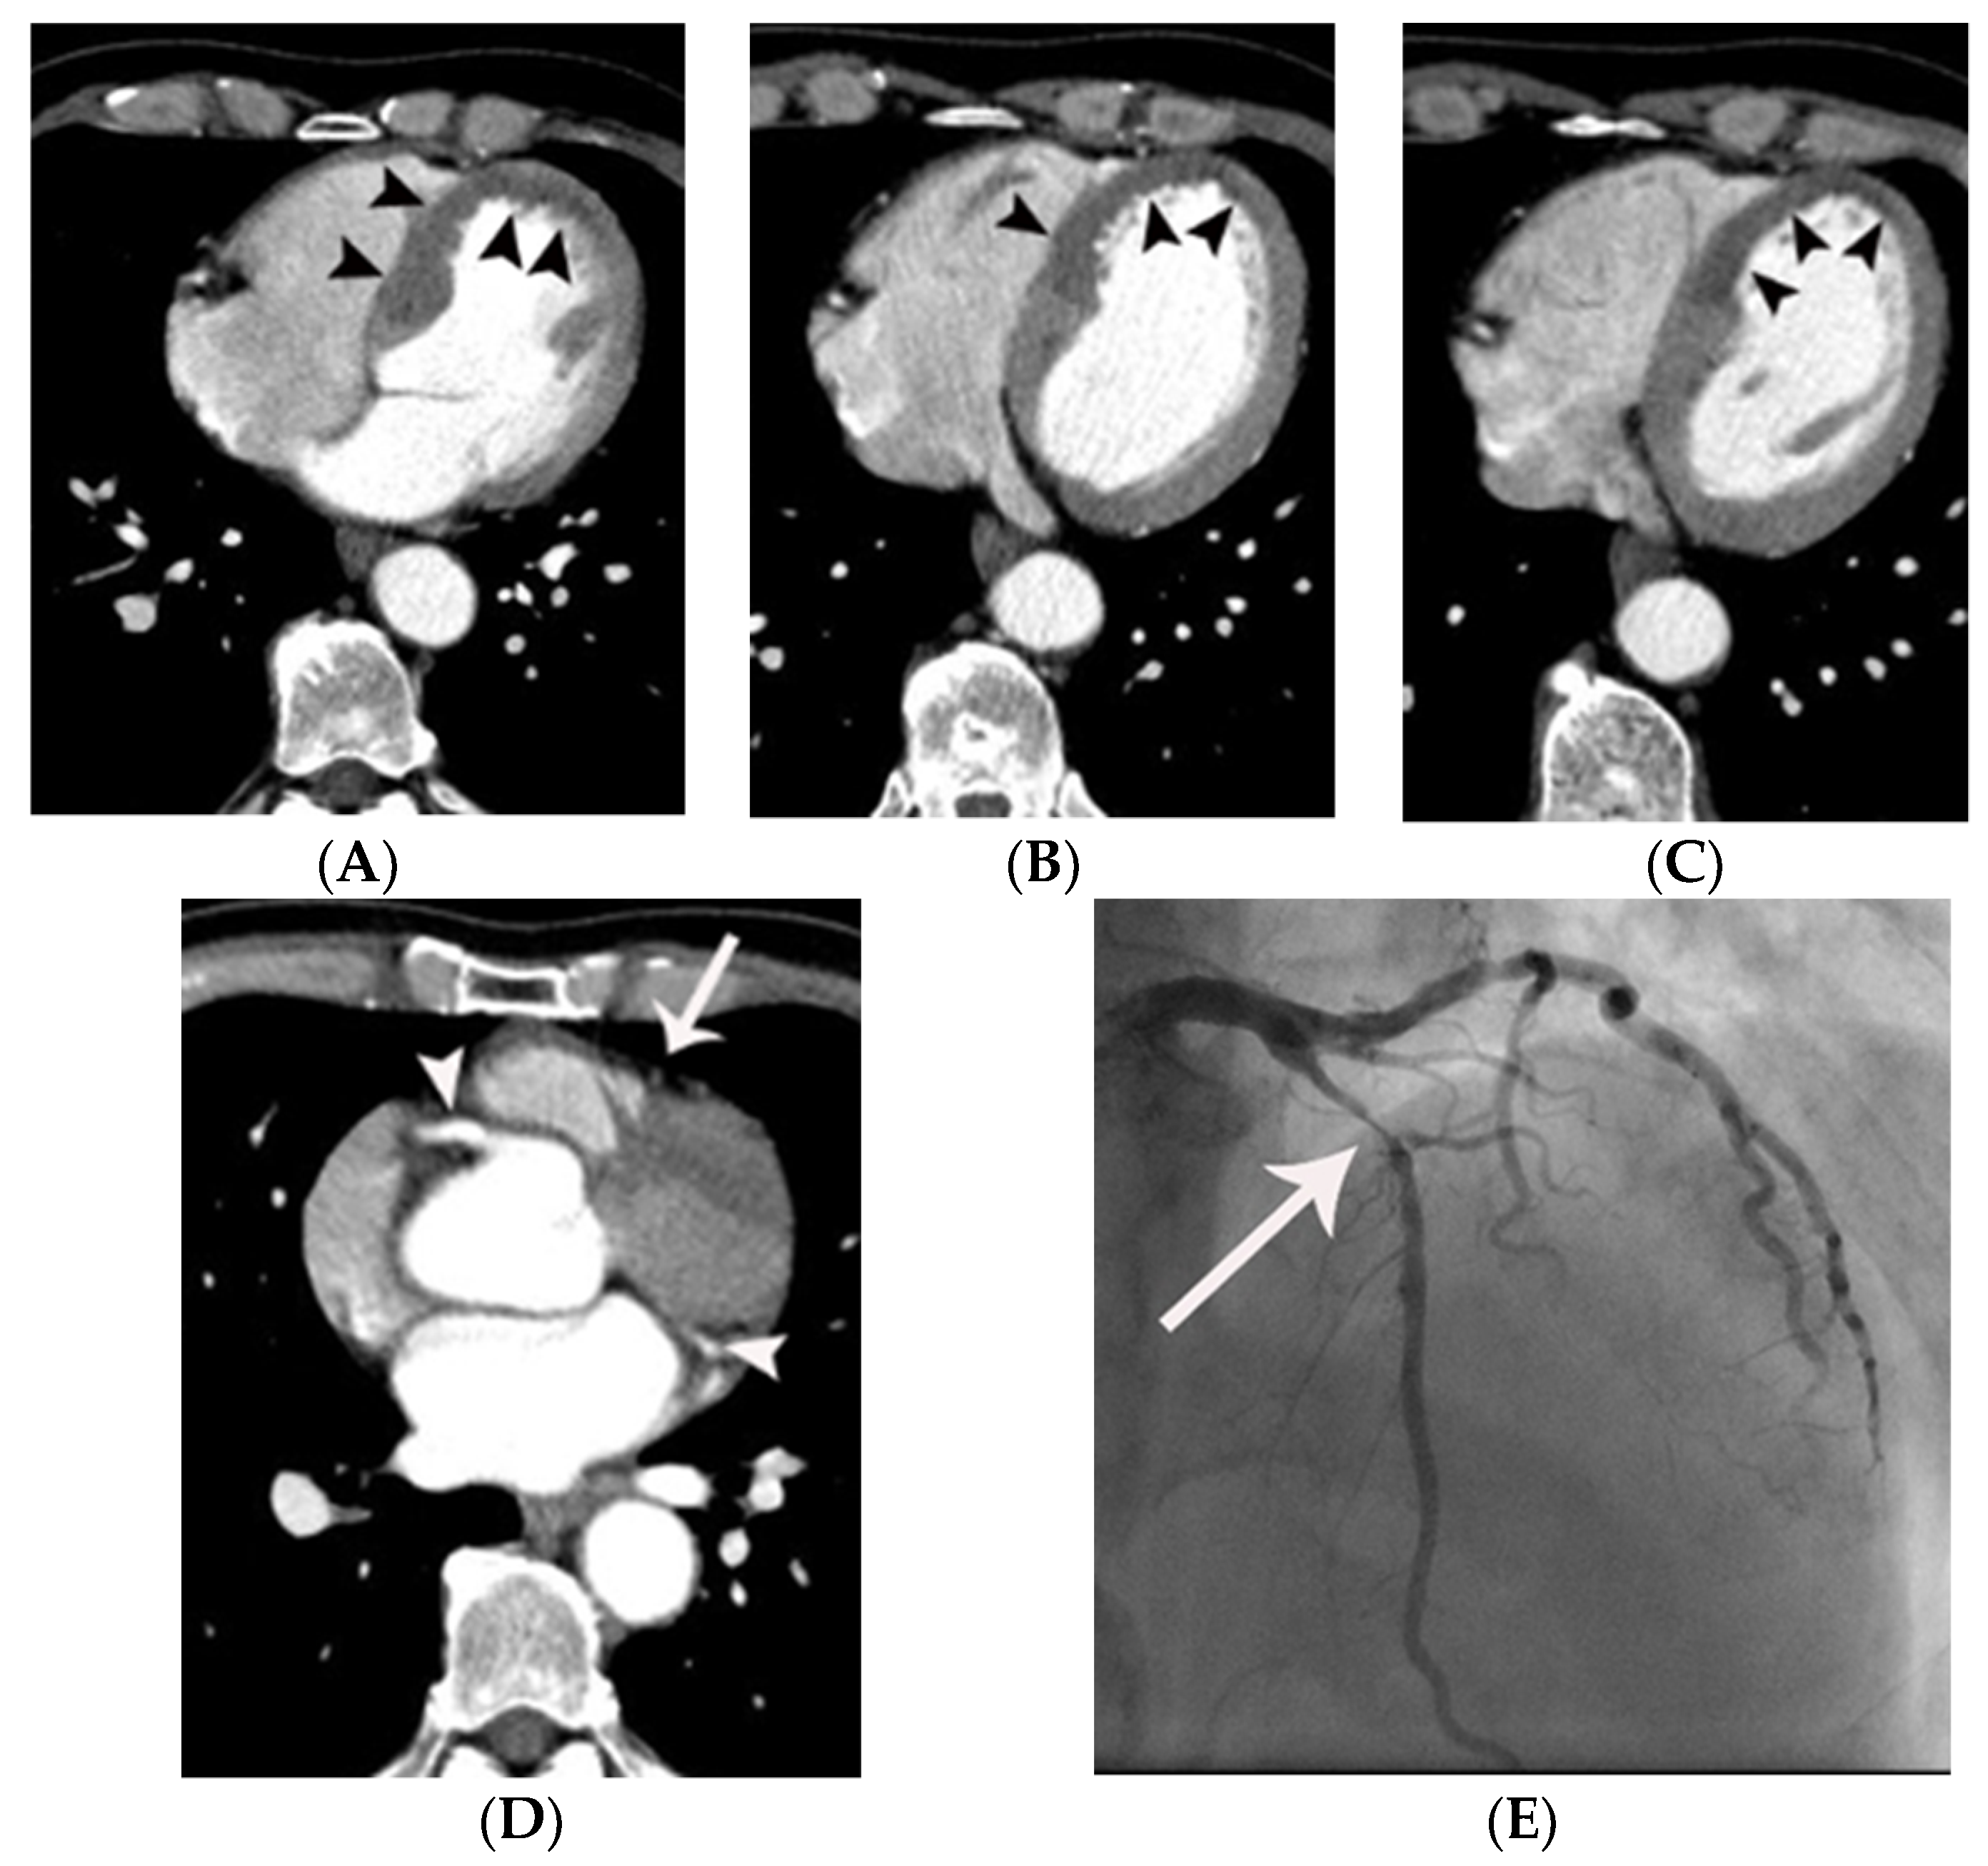

Figure 3.

Coronary artery occlusion demonstrated on non-gated enhanced chest CT in a 44-year-old man with acute myocardial infarction. (A) An abrupt cut-off (arrowheads) of contrast was noted at the origin of the left anterior descending coronary artery on an axial image at the level of the aortic root. Note that only minimal motion artifact is present in this non ECG-gated image. (B) The same finding (arrowheads) was demonstrated more clearly on a curved multi-planar reformatted image. (C) A probable myocardial perfusion defect (CT grade 2) (arrowheads) was noted in the left ventricular apex on an axial image at the level of the left atrium. (D) Subsequent coronary angiography confirmed the CT finding (arrow).